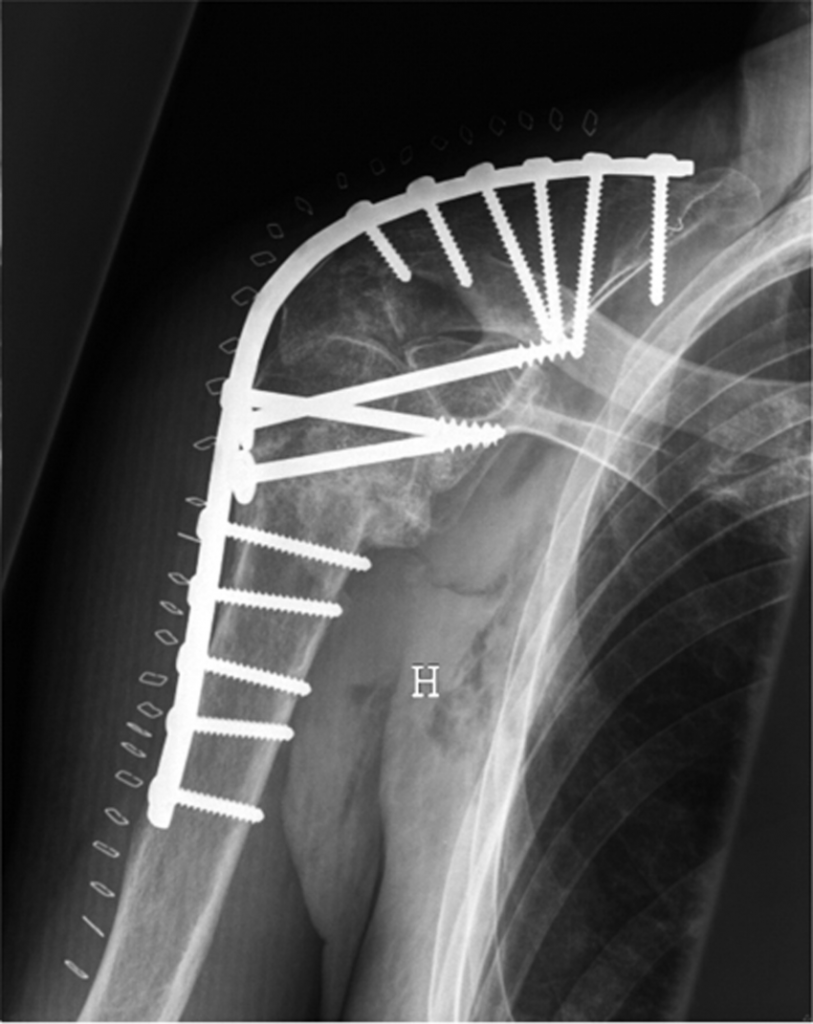

Плечевой сустав также фиксируют металлическими конструкциями:

- Винтами;

- Пластинами;

- Штыковидными гвоздями;

- Внешними фиксаторами.

Операцию проводят под наркозом. Её длительность варьирует от трёх до пяти часов. Металлические конструкции, которые внедряются в сустав, в большинстве случаев не удаляются.